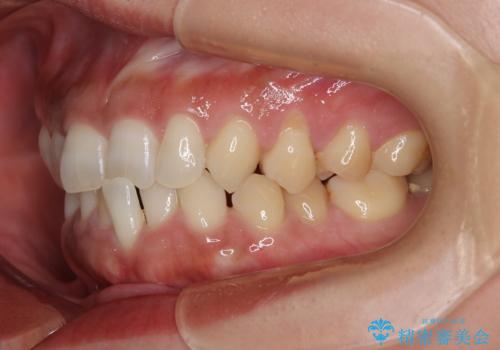

- 食いしばりと強いブラッシングにより、上顎小臼歯2本に知覚過敏を感じるようになったとのことで来院された患者様です。

歯肉退縮により歯根部が露出し、冷たい飲み物に痛みを感じる状態でした。

根面被覆を目的として歯肉移植術を行うこととしました。

歯肉が薄い状態であったため、歯肉退縮が起こりやすいと判断された患者様でした。

根面被覆を達成するとともに、歯肉の厚みを増すことで、今後歯肉退縮を起こしにくくするよう配慮した処置としました。